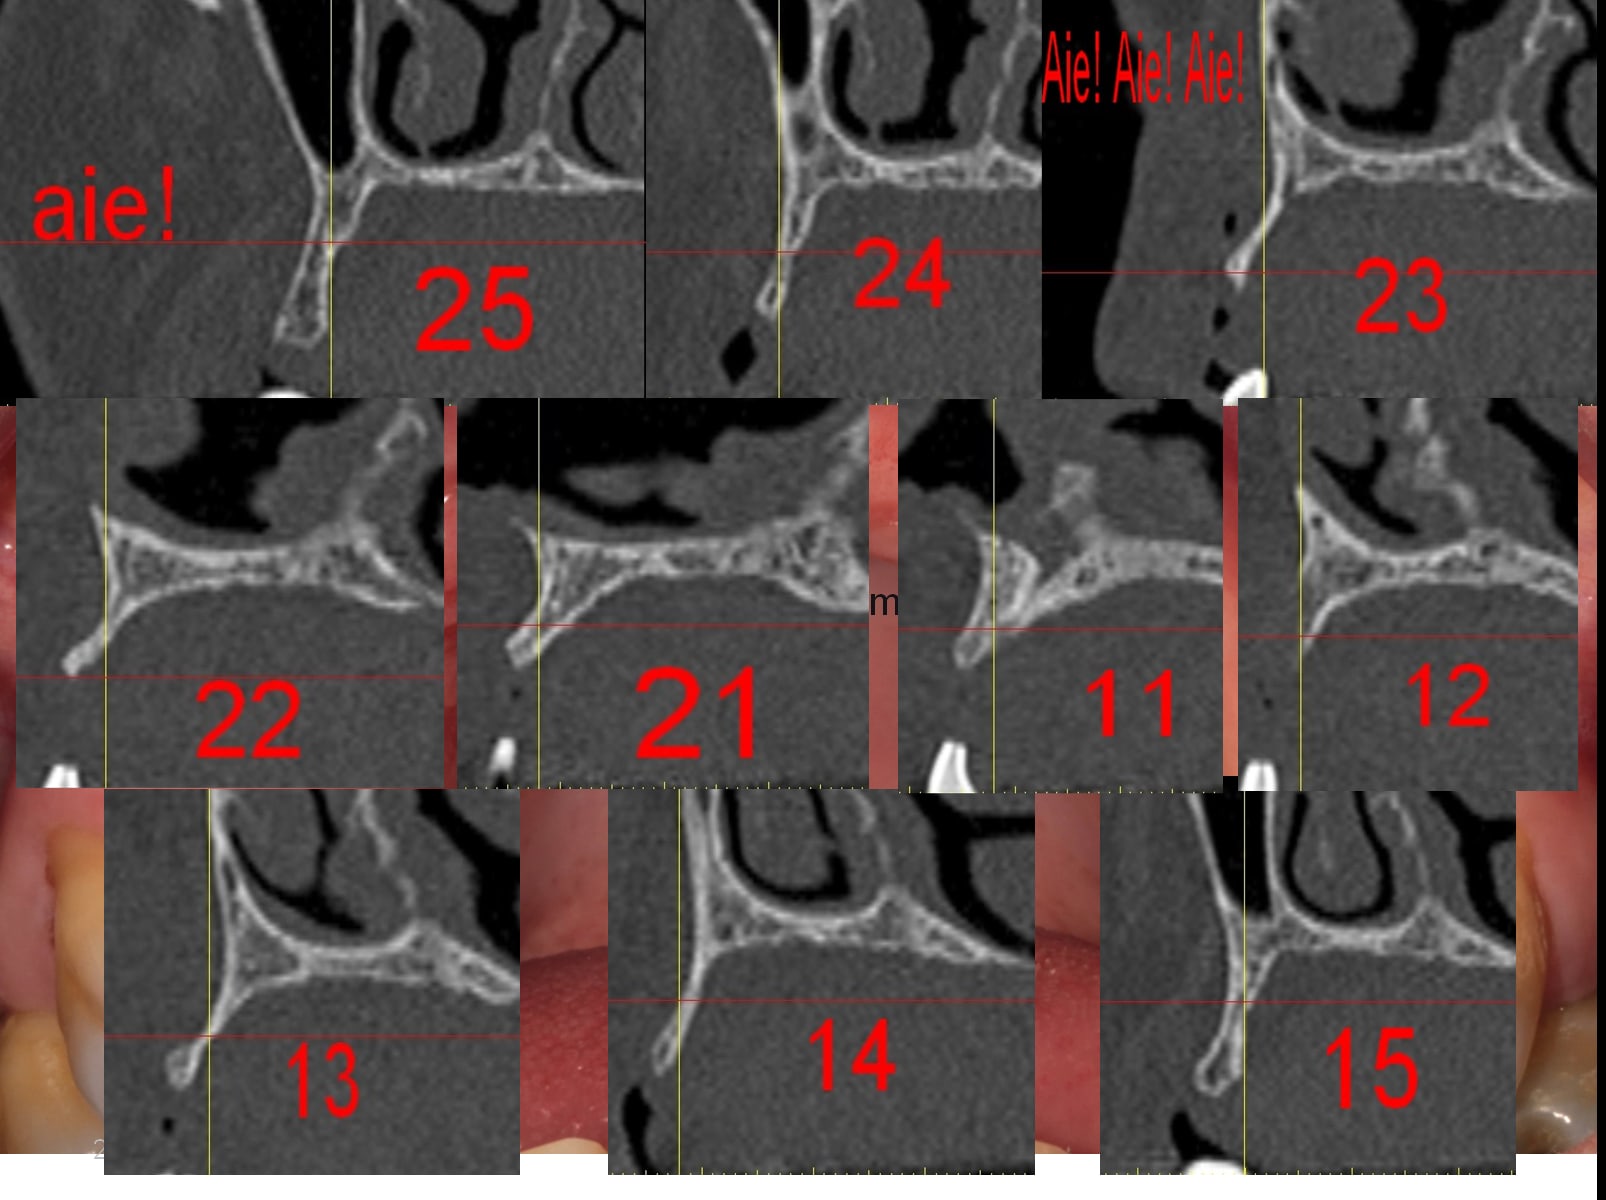

pour en finir je te passe quelques photos qui te permettront je l’espère, (?) de comprendre qu'effectivement il te reste du chemin à faire, et on ne peut le faire qu'en restant humble et surement pas en agressant les confrères qui donnent leur avis.

pour finir un petit cas sympa, fait sans guide....dis moi comment il faut faire:-)